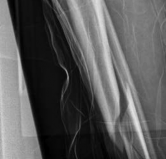

Nonunion and Delayed Union

The distal tibia has a notoriously precarious blood supply. While IM nailing preserves the extraosseous supply better than plating, the disruption of the endosteal supply during reaming can contribute to delayed union. Hypertrophic nonunions are typically managed with dynamization or exchange nailing, whereas atrophic nonunions require biological augmentation with bone grafting and potentially plate supplementation to increase stability.

Image